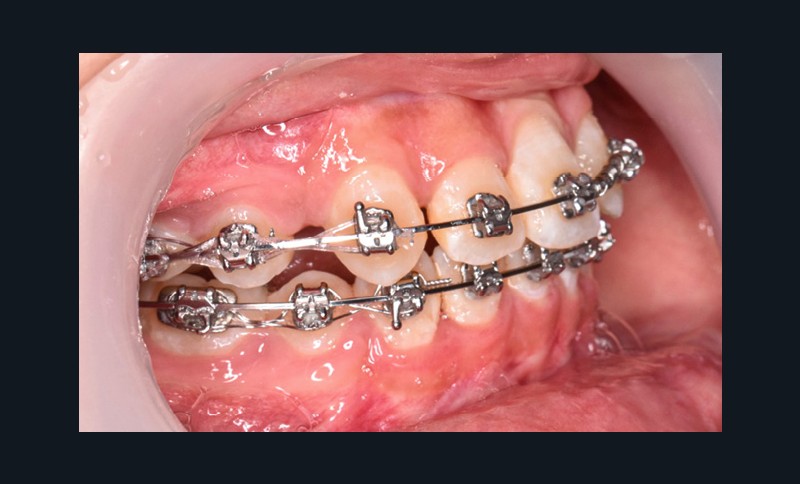

L’objectif du traitement est la correction de la DDA tout en assurant le remplacement de la 21 compromise. Décision a été prise d’extraire 34 et 44, ainsi que 21 et 14. La traction de la 23 a été réalisée à l’aide de forces légères, sur un arc transpalatin (fig. 9). Le nivellement et l’alignement, puis une mécanique par glissement ont permis d’aménager l’espace suffisant à la stratification de la canine. Elle associait un ressort en nickel-titane à des élastiques de Classe II (4 ½ oz, 3/16’’) sur un arc en acier .019×.025. Une phase d’ingression a été réalisée pour ajuster le niveau du bord libre de la canine à celui de l’incisive controlatérale (fig. 10-12).